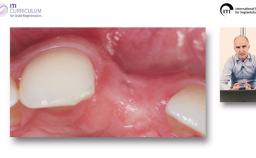

Implantatverlust mit Defektsituation: Erneute Implantation oder Alternativtherapie?

Basierend auf diversen Studien und eigener klinischer Erfahrung stellt Dieter Weingart seine Erkenntnisse und Schlussfolgerungen zum Thema Implantatverlust mit Defektbildung vor. Er illustriert das Thema mit eigenen klinischen Fällen inklusive Langzeit-follow-ups.

• die Empfehlung einer erneuten implantologischen Versorgung nach Implantatverlust mit Defektbildung diskutieren können

• Erfolgs- und Risikofaktoren einer erneuten Implantation benennen können